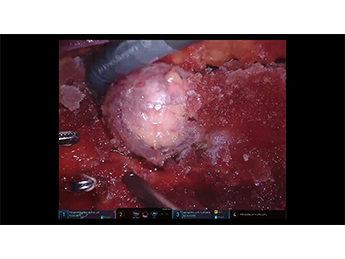

本動画では、右腎上極側の埋没腫瘍のある患者さんに対するロボットでの腎部分切除について、関⻄ろうさい病院の川端先⽣にご解説をいただいております。スラッシュアイスを […]